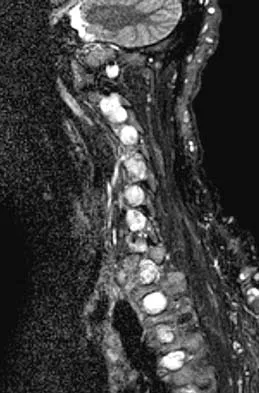

Figures 3a and 3b show the MRI scans of a patient with neck pain. What is the most likely diagnosis?

Explanation

Muliple neurofibromas result in marked foraminal enlargement as seen on the sagittal MRI scan. Collagen disorders leading to dural ectasia may show similar enlargement, but none of these is listed as a possible answer. Kim HW, Weinstein SL: Spine update: The management of scoliosis in neurofibromatosis. Spine 1997;22:2770-2776.